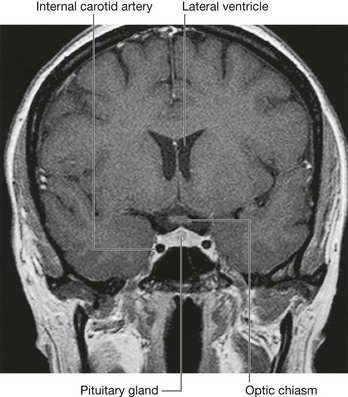

The sphenoidal sinuses are related:

image above to the cranial cavity, particularly to the pituitary gland and to the optic chiasm;

image laterally, to the cranial cavity, particularly to the cavernous sinuses; and

image below and in front, to the nasal cavities.

Because only thin shelves of bone separate the sphenoidal sinuses from the nasal cavities below and hypophyseal fossa above, the pituitary gland can be surgically approached through the roof of the nasal cavities by passing first through the anteroinferior aspect of the sphenoid bone and into the sphenoidal sinuses and then through the top of the sphenoid bone into the hypophyseal fossa.